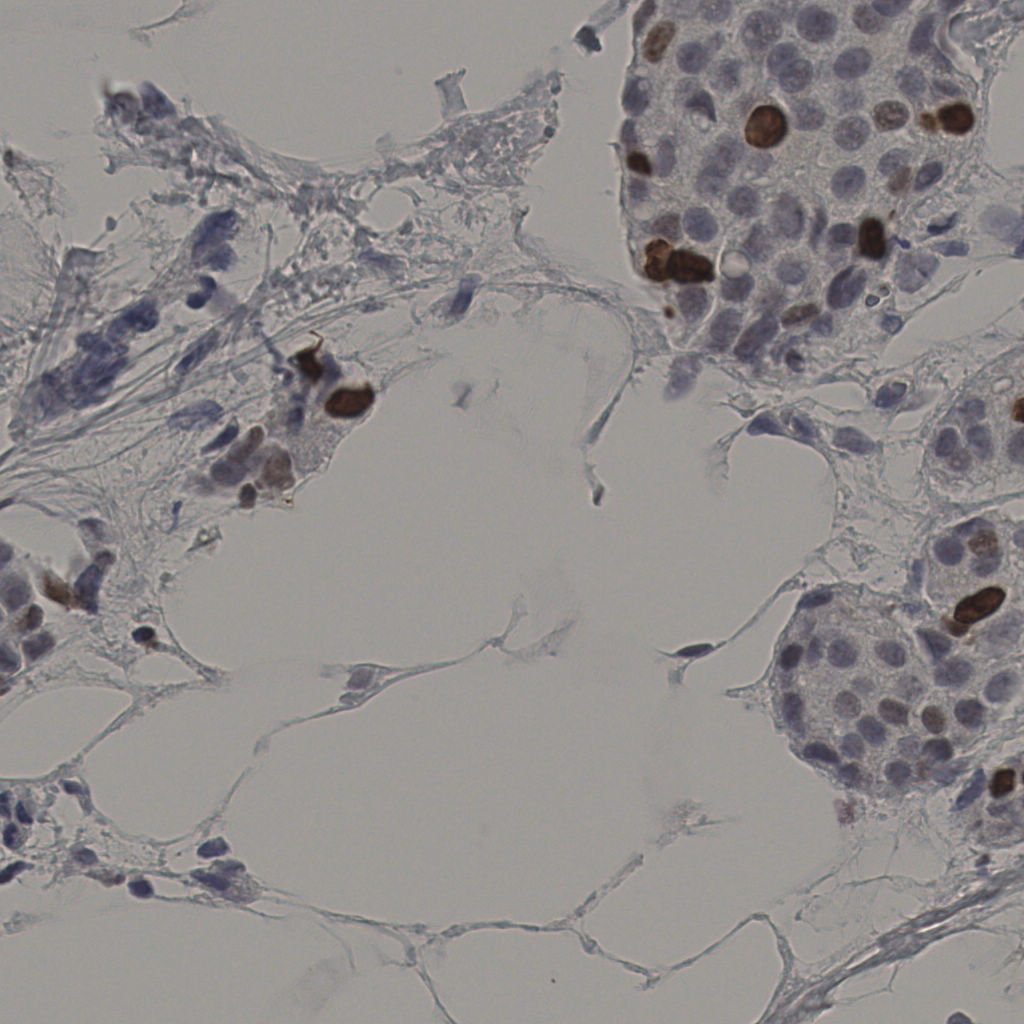

slice_37_10_x33152_y8960.png

slice_37_10_x3315...